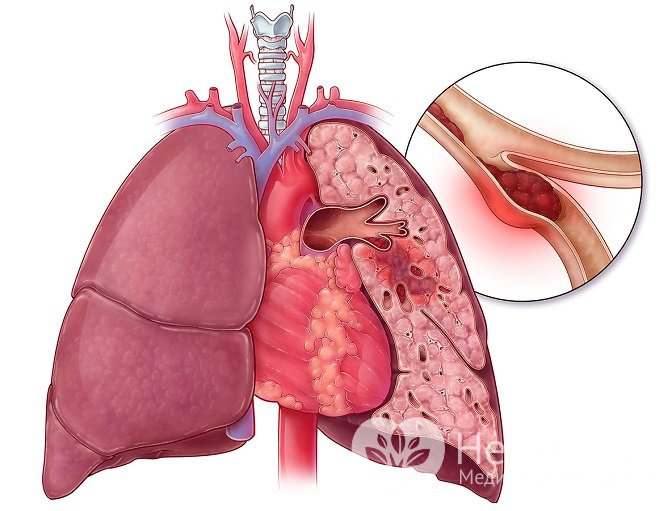

Прекращение кровотока по ветви легочной артерии приводит к развитию легочного инфарктаНарушение кровотока по легочной артерии вследствие ее сдавливания или закупорки приводит к кислородному голоданию клеток участка легкого, а впоследствии их гибели. Легкие обладают одной из наиболее развитых сосудистых сетей в организме и нуждаются в большом притоке крови. Блокирование притока в одном из сосудов приводит к системным нарушениям сердечно-сосудистой системы, вызывает повышение давления в малом круге кровообращения, может осложняться легочными кровотечениями и пневмонией. Легкое является одним из шоковых органов, то есть наиболее подверженных повреждению во время шоковых, терминальных состояний.

Инфаркт бывает ишемическим, то есть вызванным ишемией – недостаточным поступлением крови в ткани, и геморрагическим, связанным с кровоизлиянием в паренхиму легкого, как следствие, сдавливания легочной ткани.